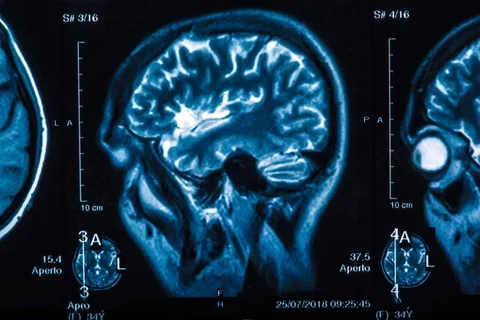

Each year, almost half of all diagnosed primary brain tumors in the United States are Grade IV glioblastoma multiforme (GBMs). While recent efforts have begun to uncover the genetic pathways involved in this cancer’s etiology – and potential methods for treatment – arguably, no specific prognostic model has arisen (and been sufficiently validated) to provide widespread usability and individually tailored predictions about a patient’s prognosis, let alone suggest optimal treatment.

This work focused on the development of a Bayesian belief network (BBN) for predicting outcomes for GBM patients. This research effort first looked to validate a BBN developed using two NIH datasets: the National Cancer Institute (NCI) Rembrandt Project; and the Cancer Genome Atlas (TCGA). Working with our clinical investigators, we developed a BBN topology for representing GBMs and to compute the required conditional probabilities from these public resources. Model variables encompassed the full spectrum of available observations (demographics, initial presentation, histopathology, treatment, imaging, performance scores, end outcomes, etc.). This Rembrandt-TCGA BBN was then evaluated against conventional statistical models (e.g., multivariate logistic regression, Cox proportional-hazards regression) to assess predictions of time to prognosis and time to survival. Next, we compared the Rembrandt-TCGA BBN’s performance against an unseen population at UCLA; this assessment informed to what extent the nationally-derived BBN could be applied to different GBM populations at other institutions. We also investigated the extension of the Rembrandt-TCGA BBN to add site-specific variables to improve prognostic predictions, including symptoms, sequelae, and additional quantitative imaging findings. The BBNs were also be extended to capture temporal information, resulting in a dynamic belief network (DBN) that represents specific phases of the cancer’s evolution and treatment. The result of this endeavor was a set of tools and awell-validated disease model to provide more tailored information and guidance to physicians about GBM patient outcomes.